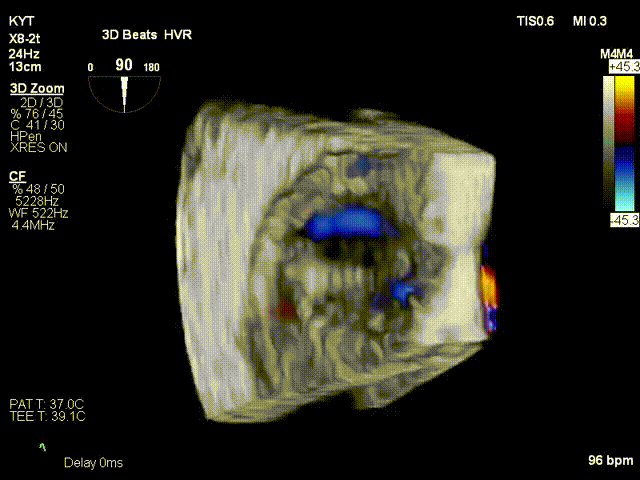

术前超声

术后超声